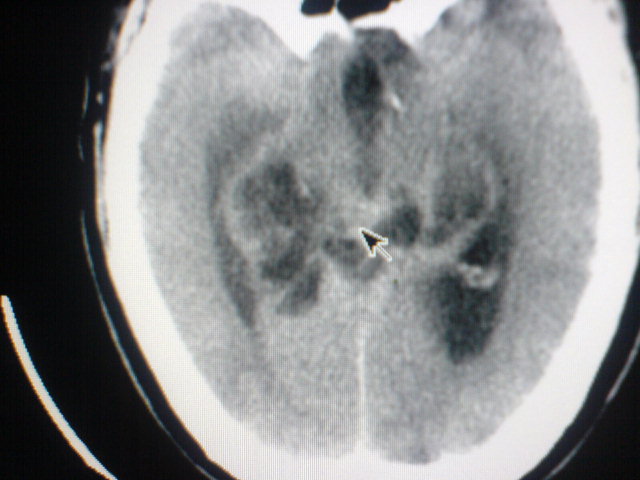

标题: CT17158:抽搐 [打印本页]

标题: CT17158:抽搐

脑积水,原因待查。

资料太少,大胆推测:脑干病变,中央孔受阻致脑脊液回流障碍脑积水。

考虑1小脑吲占位,2四脑室室管膜瘤

中线松果体区肿瘤?做增强会有帮助鉴别